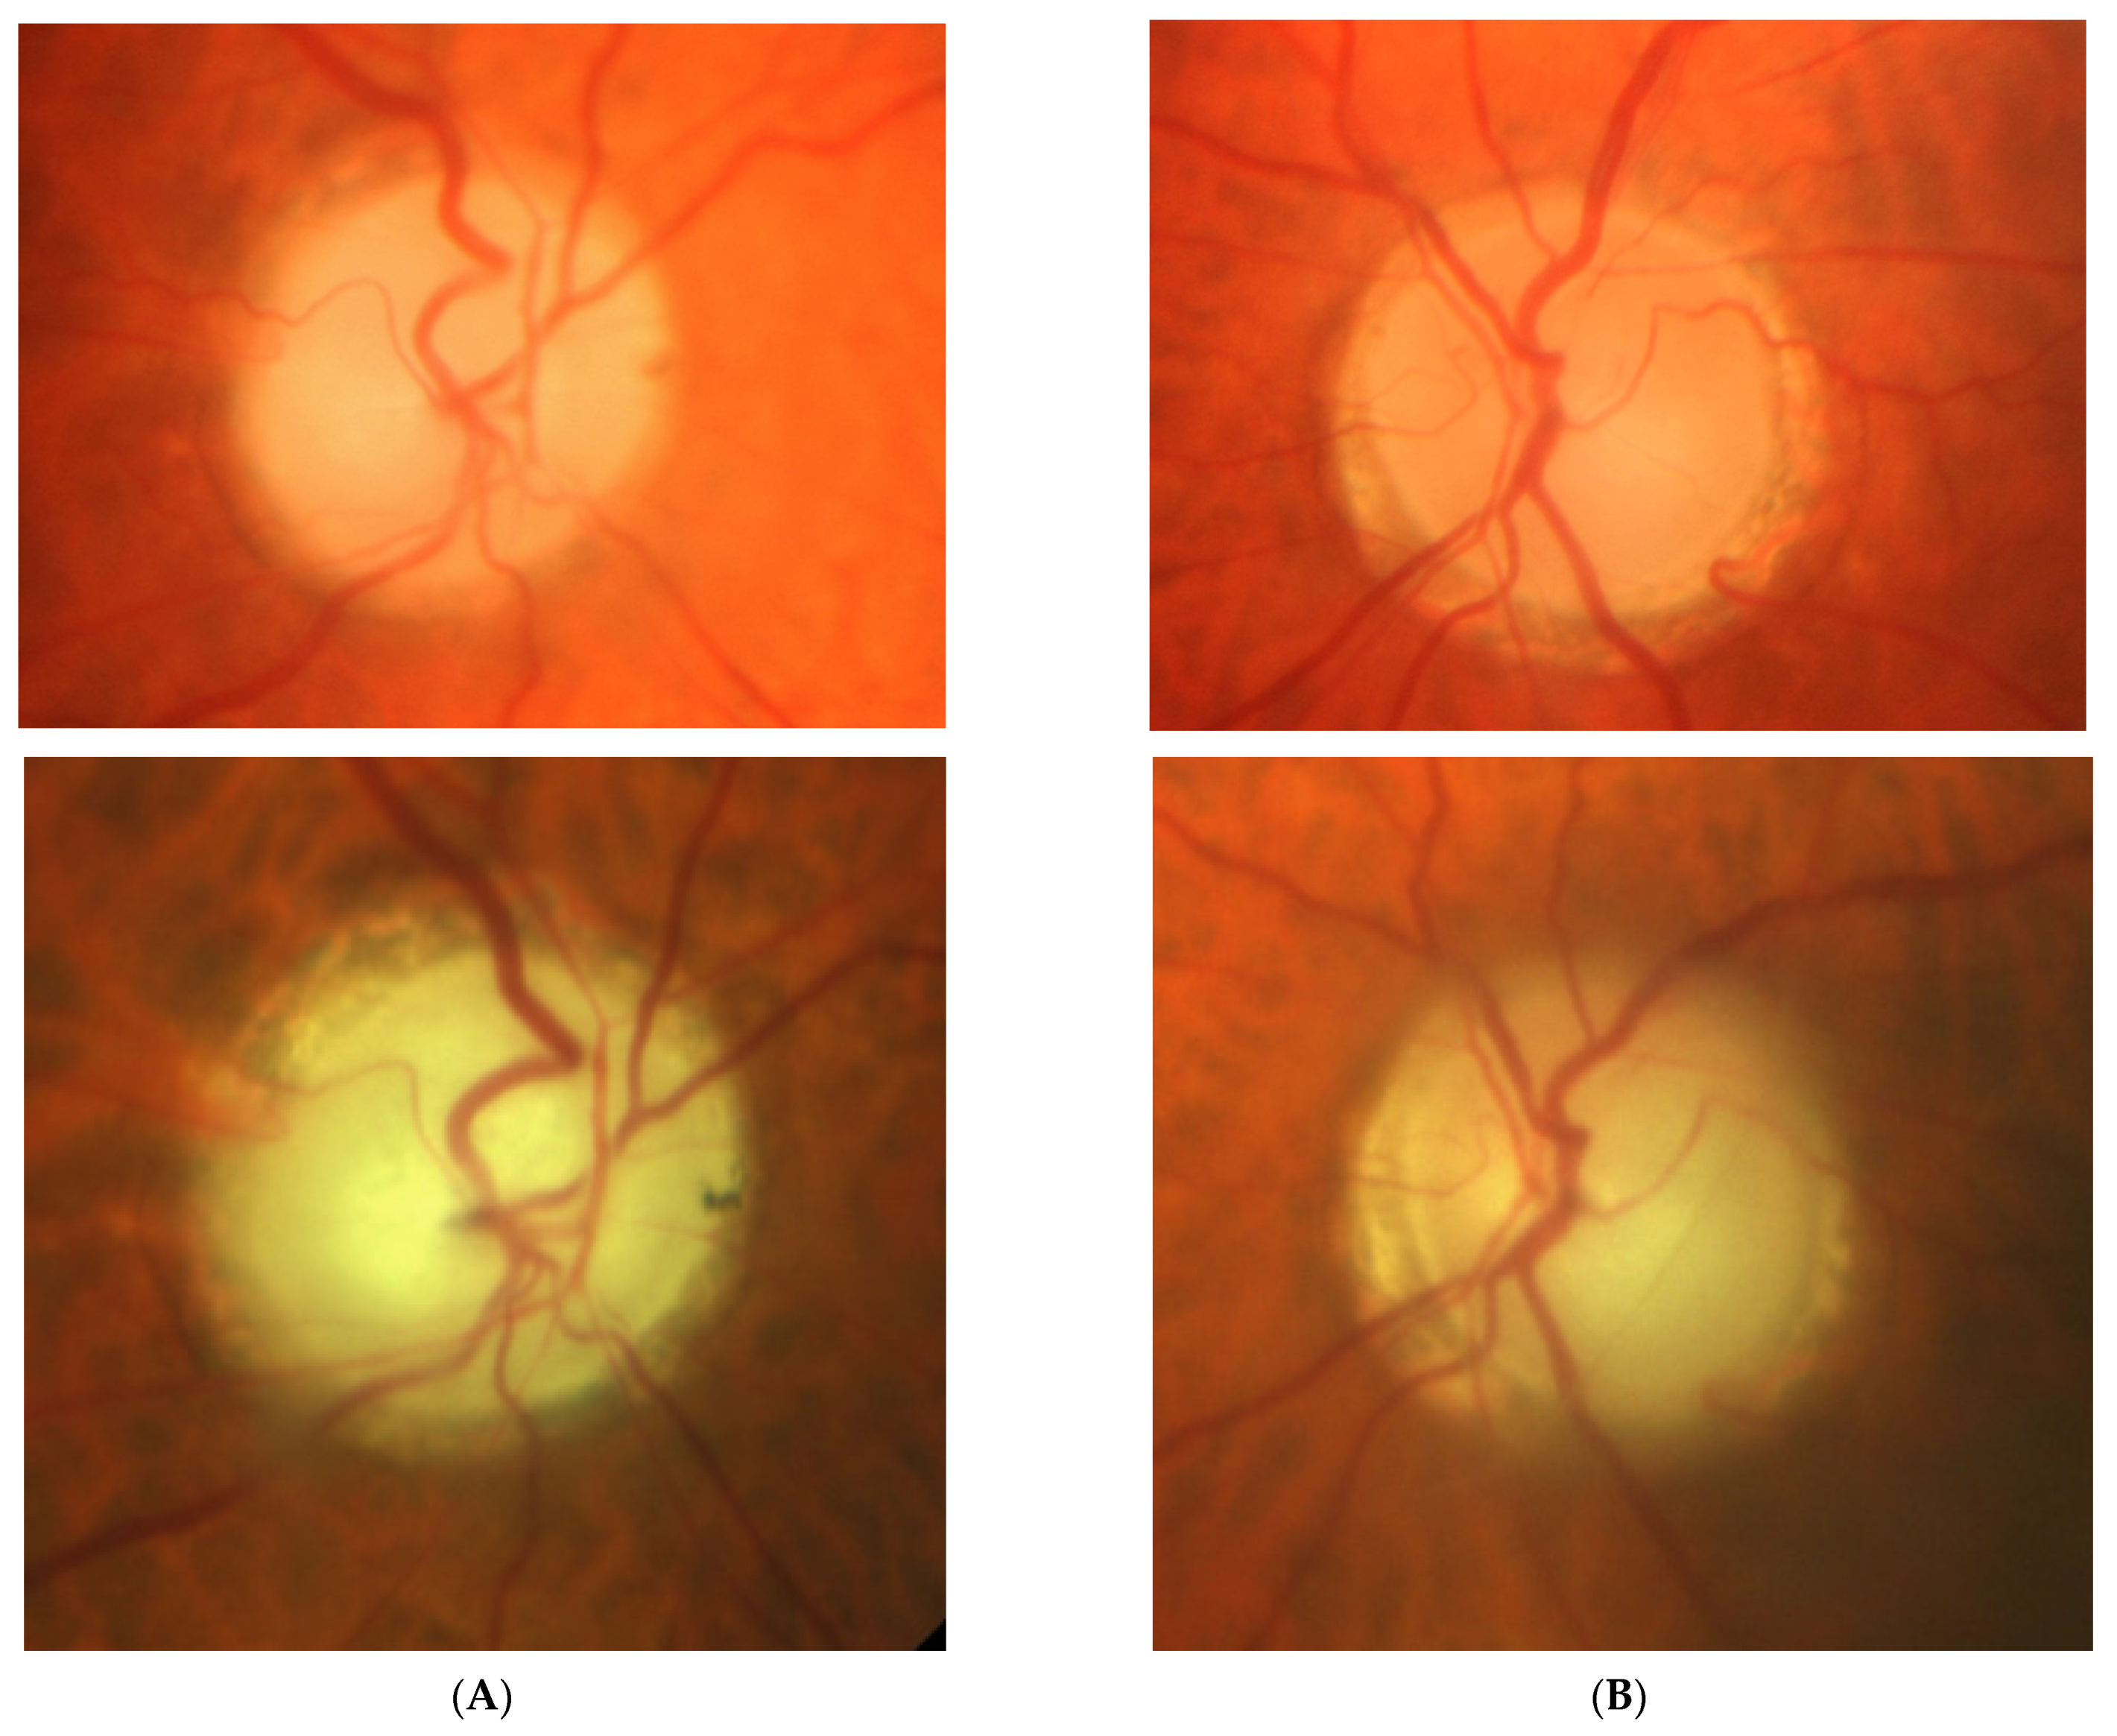

2.3. Case 3

2.4. Case 4

2.5. Case 5